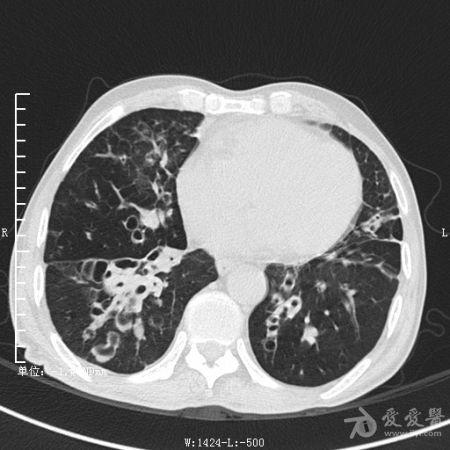

典型支气管扩张及肺水肿CT片

典型支气管扩张肺水肿